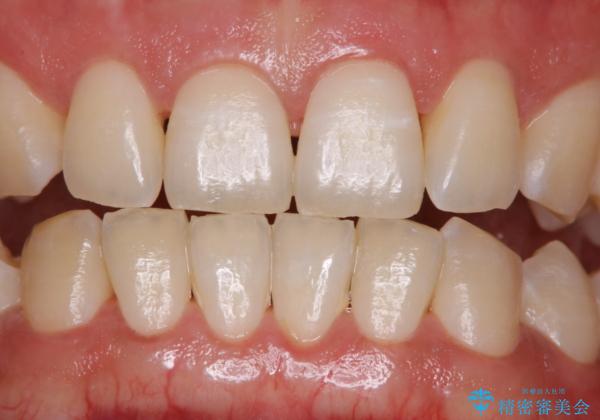

ホワイトニングせずにPMTCで明るい口元に

- ホワイトニングを考えているとのことで久しぶりに来院された方です。歯石やプラークの付着があったため、まずはPMTC60分コースを行いました。

施術後には、現状で満足とのことだったため今後は定期的なクリーニングを行っていくこととなりました。

PMTCでは、プラークや歯石、着色などを徹底的に除去します。